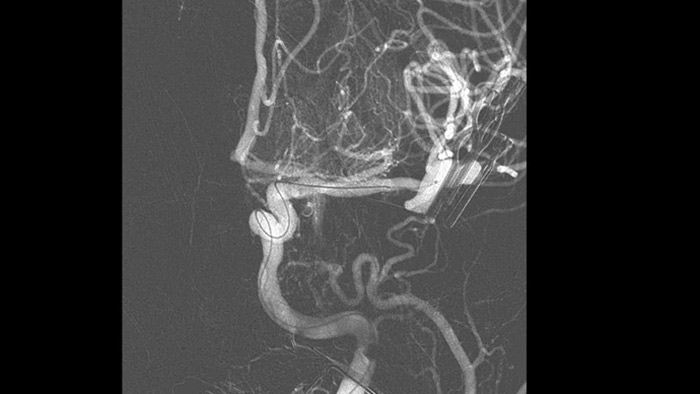

Imágenes nítidas con ASD 2D con tecnología ClarityIQ

ASD 2D con tecnología ClarityIQ

ClarityIQ aplica la compensación automática del movimiento durante la ASD en tiempo real para mantener imágenes nítidas de los vasos. Esto permite tomar decisiones con confianza durante los procedimientos para atender accidentes cerebrovasculares.

Confirmar el éxito del tratamiento

Visualización de la ASD

Las visualizaciones de la ASD de alta calidad le permiten evaluar si ha recuperado el coágulo completo y si los trozos de coágulo se han dispersado distalmente en el cerebro. Puede comprobar el restablecimiento del flujo sanguíneo en la penumbra y comprobar si hay hemorragias periprocedimiento.